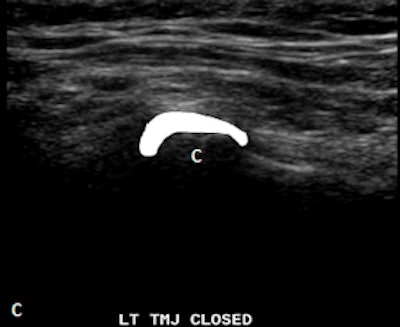

Dr. Friedman prefers that patients be supine on a stretcher with the jaw tilted away from the side to be examined. Then the person performing the ultrasound palpates the joint while the patient opens and closes her mouth. Gel is then placed on the joint, and the probe is placed at various positions around the joint. The images are examined to determine whether there is anterior displacement of the disk while the joint is the closed-mouth position.

"If the ultrasound is abnormal, the patient should be referred for an MRI, and any patient scheduled for surgery also must have an MRI," he said. "The main challenge is learning to detect what is normal on ultrasound. We also acknowledge that abnormal anteromedial and medially displaced disks may be missed or misinterpreted with ultrasound."